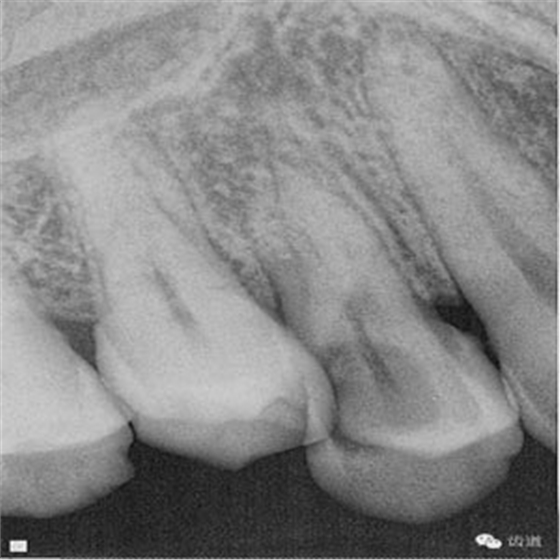

檢查:14遠(yuǎn)中鄰頜面探及齲壞至牙本質(zhì)深層,穿髓。探-,冷-,叩-。松動(dòng)-。牙齦無(wú)紅腫,未探及牙周袋。

數(shù)碼攝影x片顯示:14遠(yuǎn)中鄰頜面暗影,穿髓。根尖暗影。無(wú)牙周膜增寬。

診斷:14慢性根尖炎。